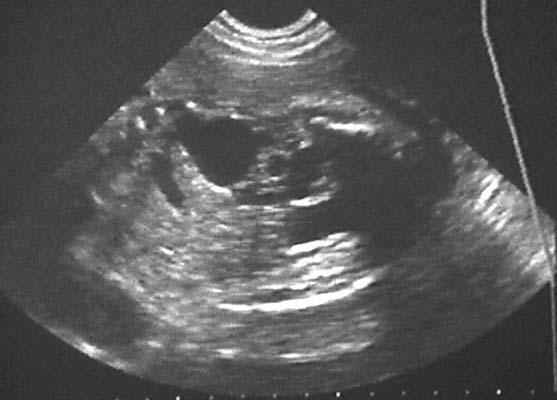

Urétéro-hydronéphrose :

Dilatation urétérale : Structure tubulée à contenu anéchogène, rectiligne ou tortueuse, pouvant présenter des variations de calibre en rapport avec le péristaltisme.

La dilatation urétérale peut parfois dépasser la ligne médiane et suggérer une origine digestive. La mise en évidence d’une dilatation calicielle permet d’évoquer plutôt une uropathie malformative.